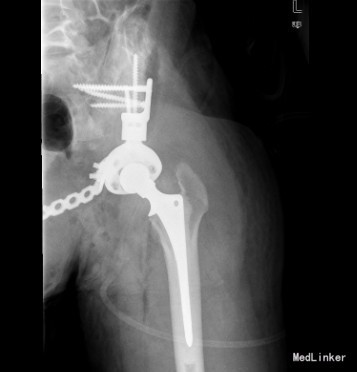

患者男,22岁,因“左臀部包块伴疼痛,进行性增大8+月”入院。入院前8+月,患者无明显诱因出现左臀部疼痛,并发现局部有包块。疼痛为钝痛,坐时加重,常反复,不伴发热及盗汗。于当地医院就诊,怀疑骨盆肿瘤;现为求进一步诊疗来我院就诊。

查体:左侧臀部内侧区隆起,局部皮肤无充血红肿,无浅静脉怒张,无皮肤破溃、皮疹及足癣。左侧臀部内侧区及左侧腹股沟区可触及巨大圆形包块,质硬,压痛明显,皮温不高,无明显触觉减退区,左足背动脉搏动正常,肢端末梢血循环正常。 辅查:骨盆CT提示左髂骨恶性肿瘤,突破皮质,边界不清,部分钙化。

初步诊断:左侧骨盆骨肉瘤(Ⅰ+Ⅱ+Ⅲ区) 诊疗计划:完善术前抽血常规、心电图及胸片等检查后择期手术治疗。

已行左侧骨盆肿瘤切除活检+左半骨盆置换术。由于骨盆区解剖结构复杂,骨盆恶性骨肿瘤的保肢手术极具挑战性。早期文献报导的致死性并发症高达10%,总体并发症更高达75%,5年生存率约为 25%-35%;目前随着技术进步预后相对较好一些。